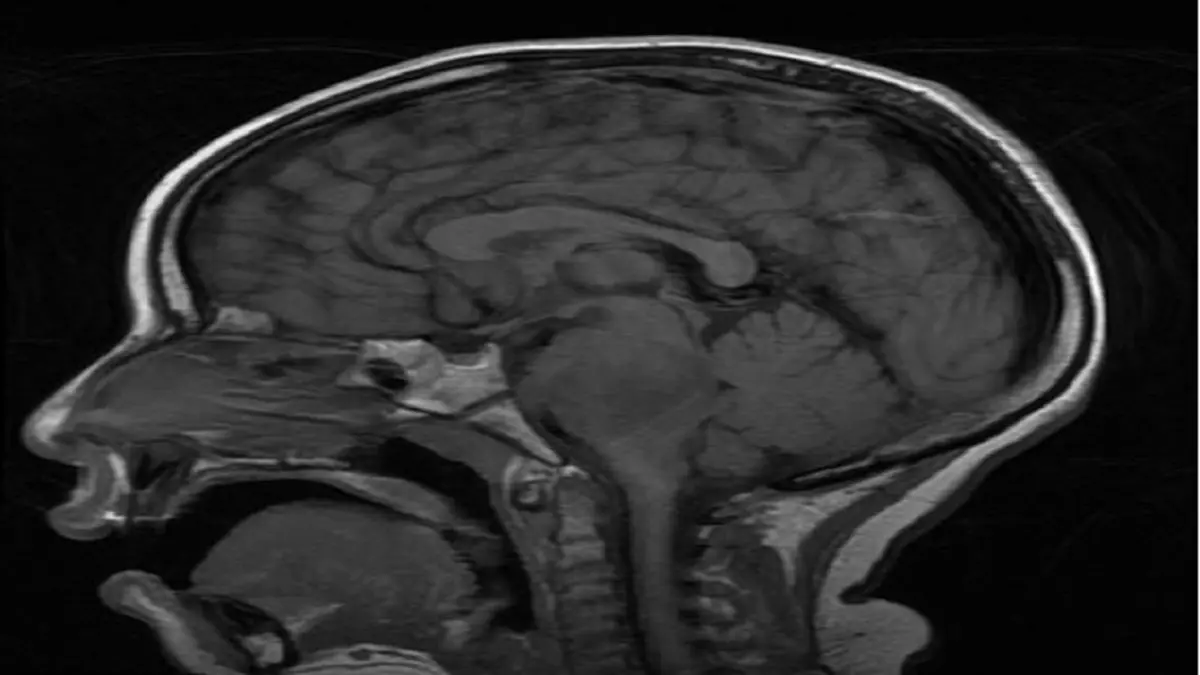

وتنمو أورام DIPG في الجزء العلوي من الحبل الشوكي وتنتشر خلال جذع الدماغ؛ مما يجعل من المستحيل إزالتها جراحيًا أو بالخزعة لإجراء تحليل.